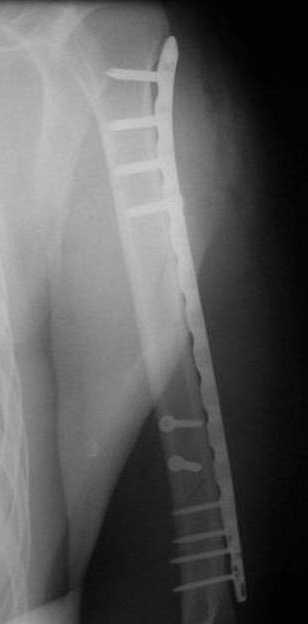

Несмотря на высокоэнергетический характер ранения, пуля не попала непосредственно в кость, а прошла рядом. Таким образом, для бедренной кости это ранение нельзя назватьв полном смысле этого слова высокоэнергетическим. К сожалению, не видно выходное отверстие. В любом случае, при таком переломе интрамедуллярный остеосинтез вполне показан. Кроме того, если пациент попал к Вам в первые часы после ранения, рана не должна рассматриваться как инфицированная. В качестве примера возможности даже более травматичной операции при таком характере перелома привожу следующий случай.

Пациент оперирован на 5-е сутки (переведен из другого лечебного учреждения)после сквозного пулевого ранения плеча и грудной клетки (непроникающее ранение той же пулей). Выполнен минимально инвазивный остеосинтез блокируемой метадиафизарной пластиной, повторная хирургическая обработка ран плеча. Заживление всех ран первичное, сращение наступило в обычные сроки.